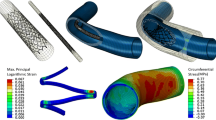

An alternative strategy is the use of a flow diverting stent, i.e. a bare stent with high strut density. In cerebral aneurysms, flow diverters effectively reduce flow in the aneurysm and promote aneurysm thrombosis and subsequent shrinkage [4]. PAA can be treated in this fashion using the Supera interwoven nitinol stent [5] (Abbott, Santa Clara, CA). During deployment, the stent can be locally compressed to achieve a high mesh density (Fig. 1; Video 1), creating a flow diverting configuration that can be augmented by using multiple Supera stents. In two PAA cohorts treated with 1–3 Supera stent layers, the 1-year patency was 85–100% and at median 44-month follow-up, patency was 67% [5, 6]. Aneurysm thrombosis was seen in 88% within a week, and in 100% through 4-month follow-up [5]. Potential advantages include increased flexibility with respect to diameter transitions and patency of overstented side-branches.

Segmentations (top) and photographs (bottom) of the four stented models. A straight inlet with single Supera stent; the top-down barrel view in the right-down insert shows the tortuous stent trajectory, B straight inlet with dual-lined Supera stent, C bent inlet with single Supera stent, D bent inlet with dual-lined Supera stent. Video 2 shows the deployment of the Supera stent in the phantom

For both anatomies, three stent configurations (no stent, single lining and dual aneurysm lining) were established. Single stent deployment with maximal strut compression in the aneurysm resulted in a helical stent trajectory and a simpler curved stent trajectory in the straight and bent anatomy, respectively (Fig. 2, Video 2). The dual stent deployment led to a straightened stent trajectory in the straight anatomy, whereas the curved trajectory in the bent anatomy was unaltered.